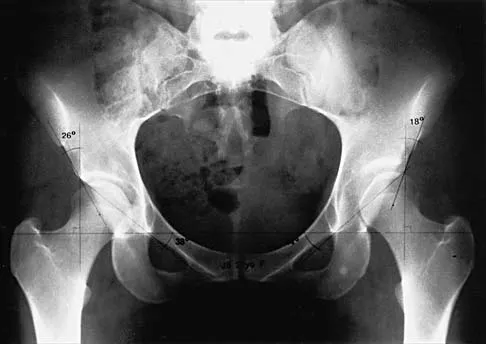

Figures 39a and 39b show the radiographs of an otherwise healthy 10-year-old boy who has had thigh pain and a limp for the past 9 months. Examination reveals that the left lower extremity is 1 cm shorter, with reduced flexion, abduction, and internal rotation on the left side. The patient is at the 50th percentile for height and the 90th percentile for weight. Serum studies will most likely show

The patient has a slipped capital femoral epiphysis (SCFE) at a younger than average age (average age 13.5 years for boys and 12.0 years for girls); therefore, an etiology that is not idiopathic must be considered. Hypothyroidism can result in a SCFE, but these children typically fall into the category of less than the 10th percentile for height. SCFE may develop in children with a growth hormone deficiency who have undergone hormonal replacement. Osteodystrophy caused by chronic renal failure may result in a SCFE, but the bone quality is markedly osteopenic on radiographs and the children are chronically ill with both low height and weight percentiles. An elevated estrogen level results in physeal closure and is protective to physeal slippage. Therefore, this child will most likely have normal laboratory values. Loder RT, Hensinger RN: Slipped capital femoral epiphysis associated with renal failure osteodystrophy. J Pediatr Orthop 1997;17:205-211.